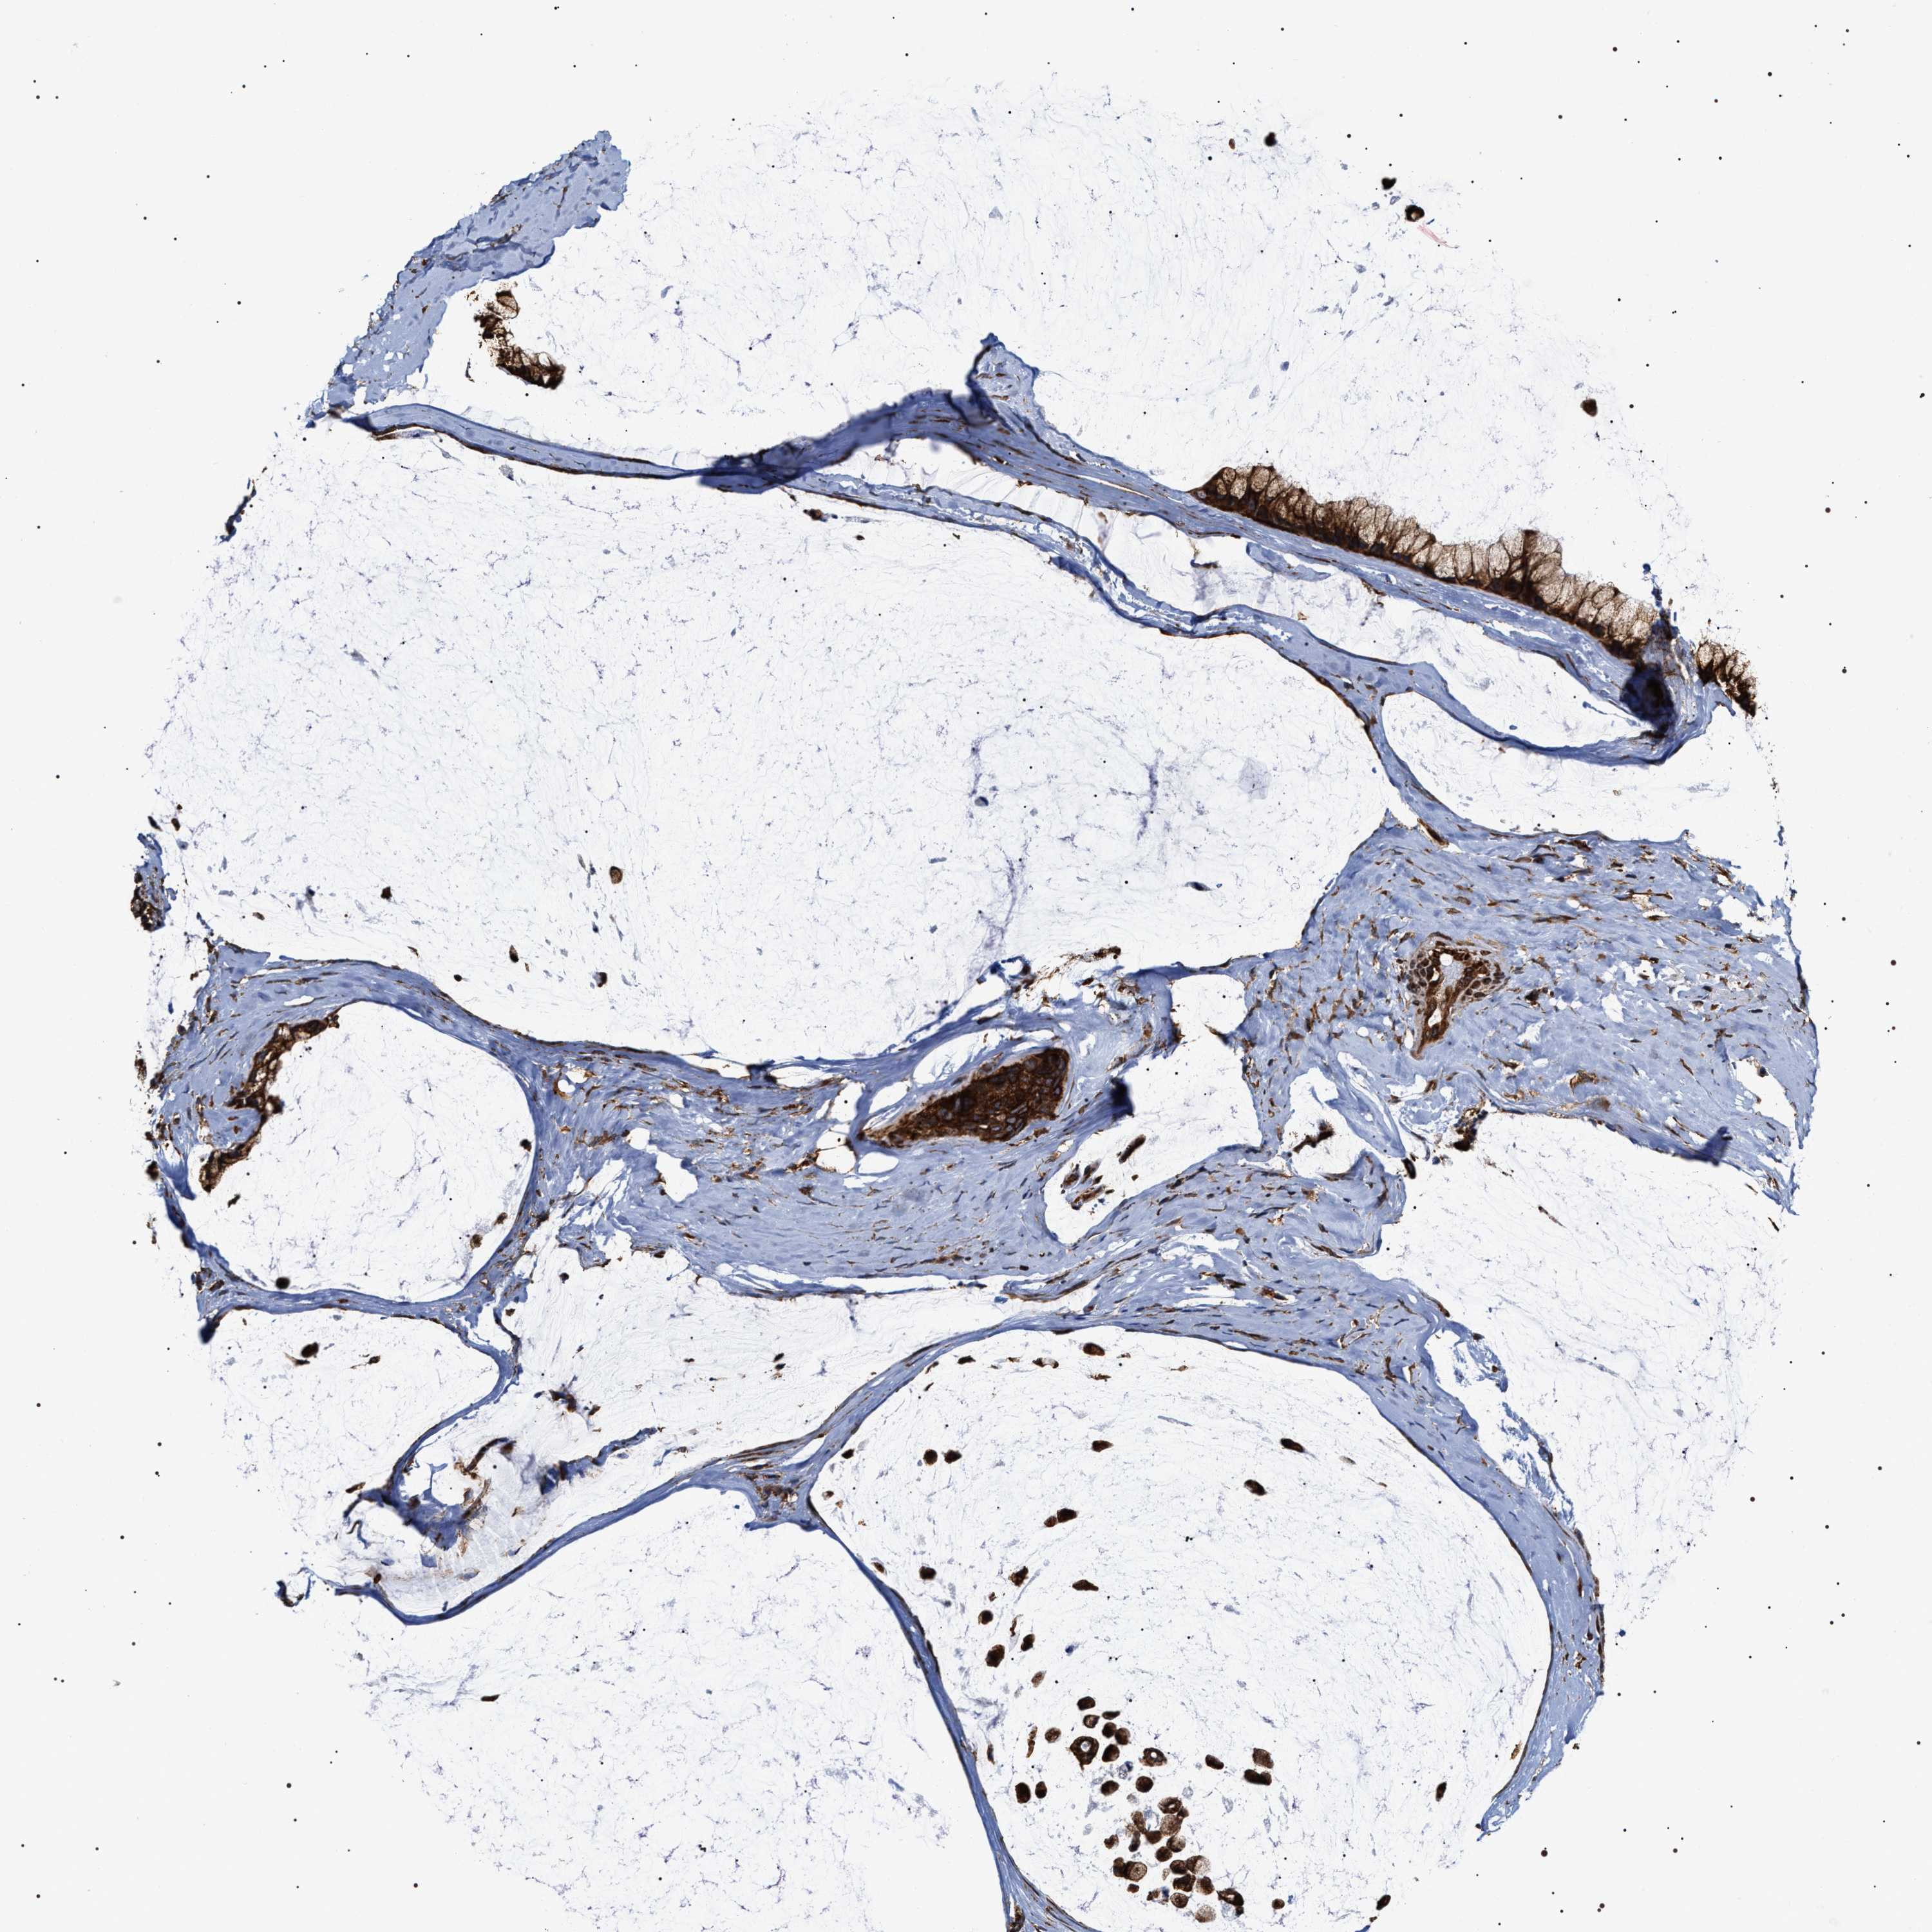

OVARIAN CANCER - Protein expressioni

A mouse-over function shows sample information and annotation data. Click on an image to view it in a full screen mode. Samples can be filtered based on level of antibody staining by selecting one or several of the following categories: high, medium, low and not detected. The assay and annotation is described here.

Note that samples used for immunohistochemistry by the Human Protein Atlas do not correspond to samples in the TCGA dataset.

Antibody stainingi

Antibody staining in the annotated cell types in the current human tissue is reported as not detected, low, medium, or high, based on conventional immunohistochemistry profiling in selected tissues. This score is based on the combination of the staining intensity and fraction of stained cells.

Each image is clickable and will lead to virtual microscopy that enables deeper exploration of all samples and also displays staining intensity scores, fraction scores and subcellular localization as well as patient and tissue information for each sample.

Antibody HPA020559

Antibody CAB026297

Cystadenocarcinoma, serous, NOS

Carcinoma, endometroid

Cystadenocarcinoma, mucinous, NOS

Carcinoma, NOS